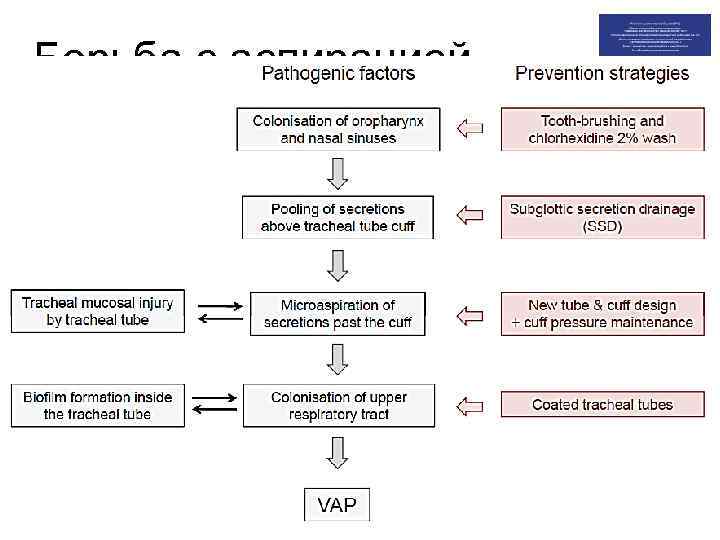

Борьба с аспирацией чистим зубы полощем рот «особенные» трубки дренаж над манжеткой новые трубки и манжетки импрегнированные трубки

Борьба с аспирацией чистим зубы полощем рот «особенные» трубки дренаж над манжеткой новые трубки и манжетки импрегнированные трубки